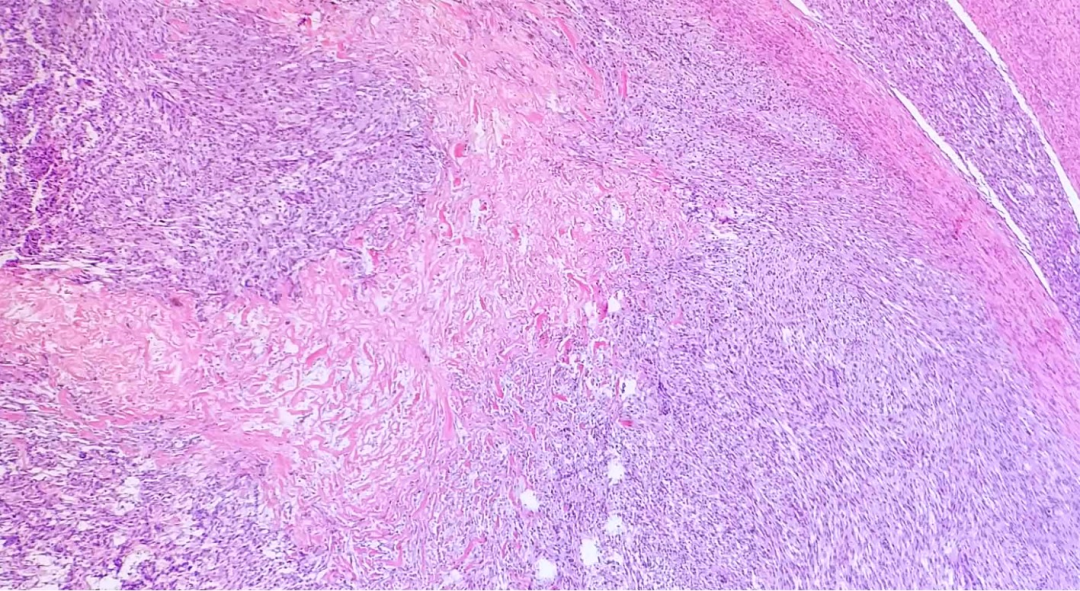

1.凝固性坏死,表现为多灶性不规则坏死,典型者呈地图样或岛屿样改变。与周围未坏死组织分界清晰,陡然出现而缺乏过渡,坏死区内可见肿瘤细胞残影,血管结构常保留,周围常残留一些存活的肿瘤细胞,坏死灶周围缺乏炎症和肉芽组织增生、纤维化等修复反应。

需与良性平滑肌瘤及恶性潜能未定的平滑肌肿瘤鉴别,主要依靠凝固性坏死(首要指标)存在与否、细胞核异型及核分裂活性这三个方面进行鉴别。良性平滑肌瘤中出血性梗死变性区多呈片状分布,镜下广泛均质红染,无细胞残影及血管残留,变性区周边部可见变性与正常过渡区域并常伴炎症反应及成纤维细胞增生等修复性反应。还需与其他一些原发于子宫的肉瘤鉴别,如未分化肉瘤或癌肉瘤。